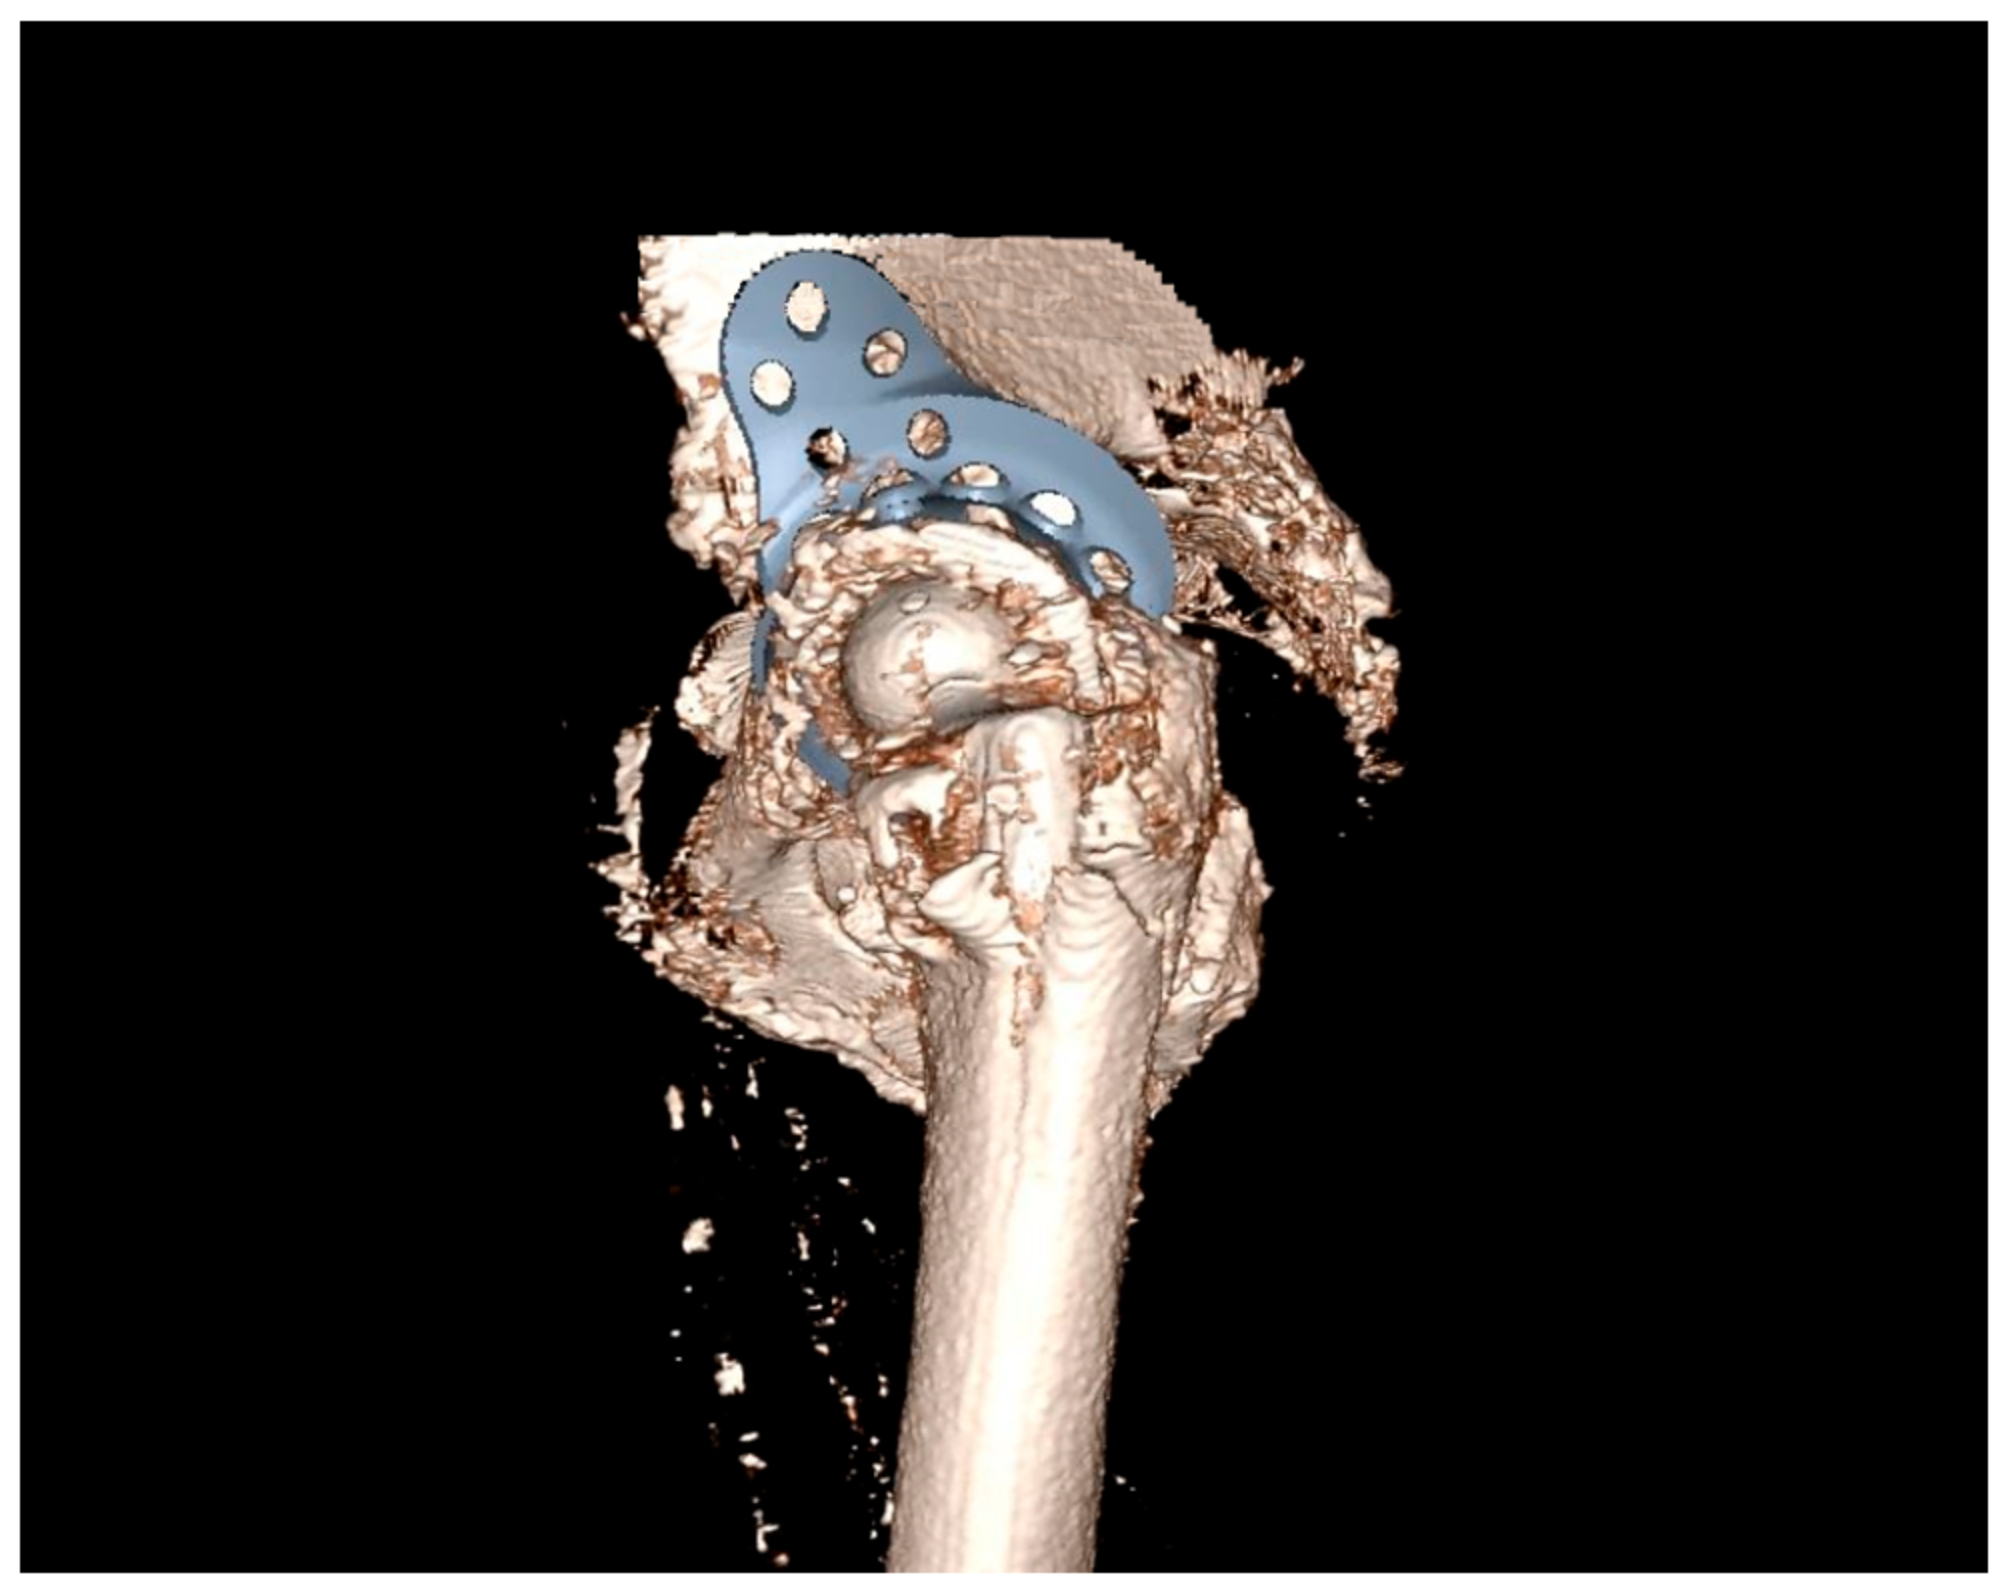

Figure 2. Personalized 3D templating using 3D Joint Sectra (Sectra AB, Linköping, Sweden) planning software (version 24.2.6). Planning aimed to bridge the granuloma in the area of the acetabular dome using the proximal flange of the Burch Schneider reinforcement cage.